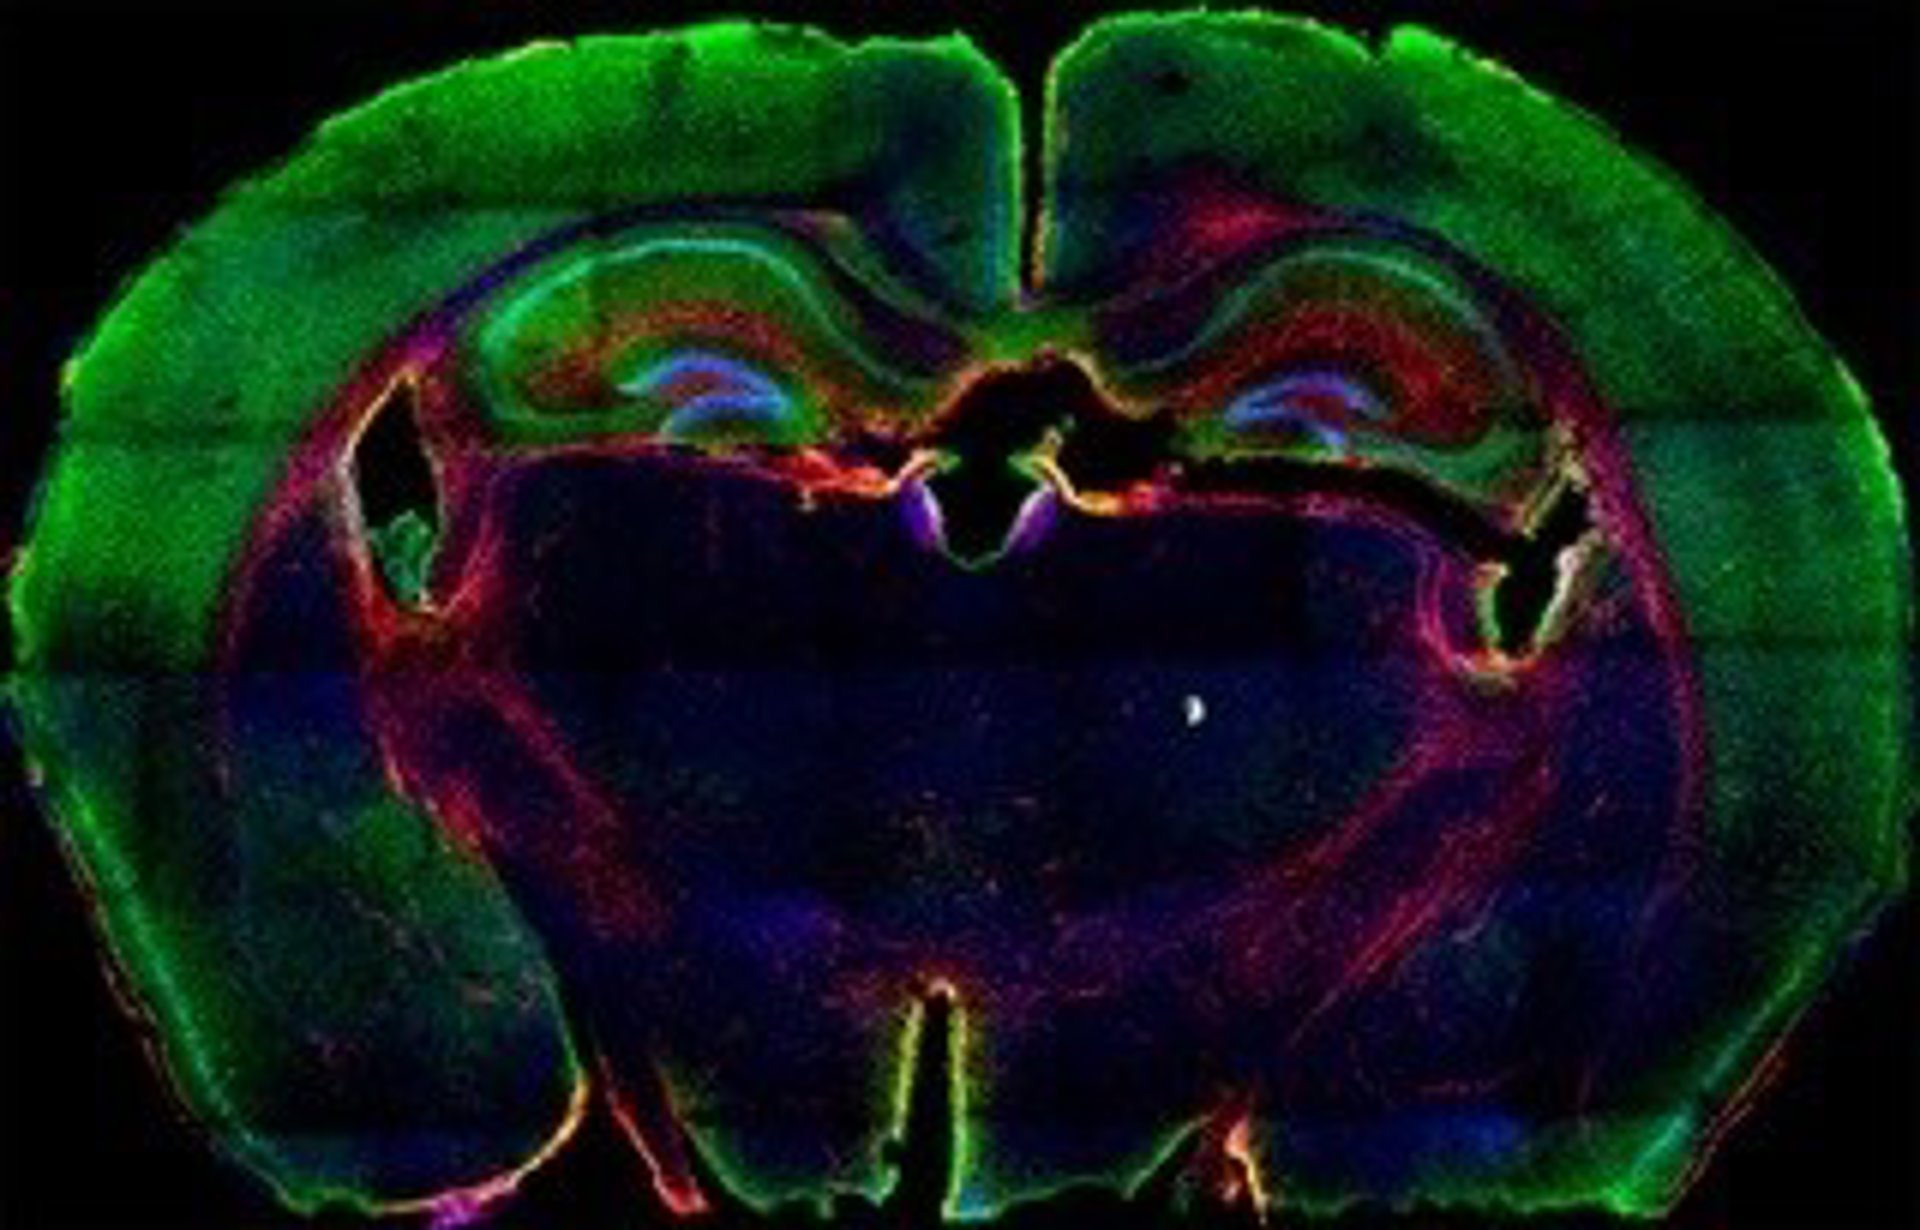

Archivo - Glioma

Archivo - Glioma - CNIO - Archivo